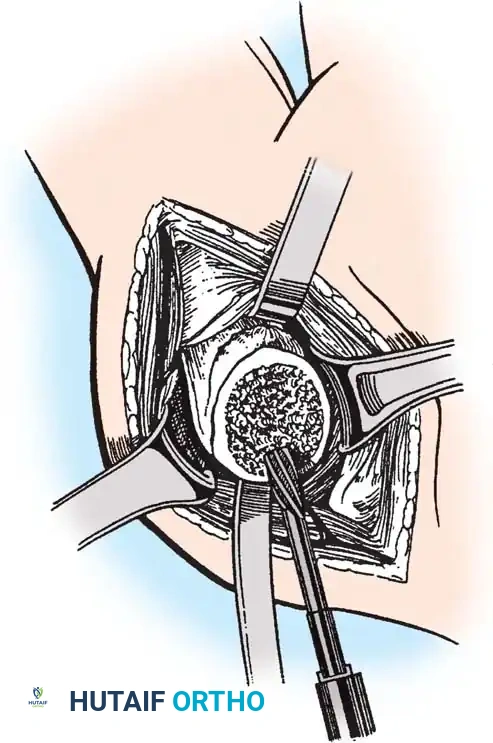

3. Humeral Head Resection

Dislocate the humeral head anteriorly through external rotation and extension. Remove peripheral osteophytes to identify the true anatomical neck. The humeral cut is made along the anatomical neck, typically at 30 degrees of retroversion and 45 degrees of inclination.

4. Glenoid Preparation

Excellent exposure is critical. Release the inferior capsule completely from the glenoid rim.

* Identify the center point of the glenoid.

* Perform concentric reaming to correct version and create a bleeding bone bed.

* Pitfall: Avoid excessive reaming, which penetrates the dense subchondral bone plate and enters the weaker cancellous vault, leading to catastrophic early subsidence.

Cement the all-polyethylene glenoid component using pulsatile lavage, meticulous drying, and pressurization techniques.